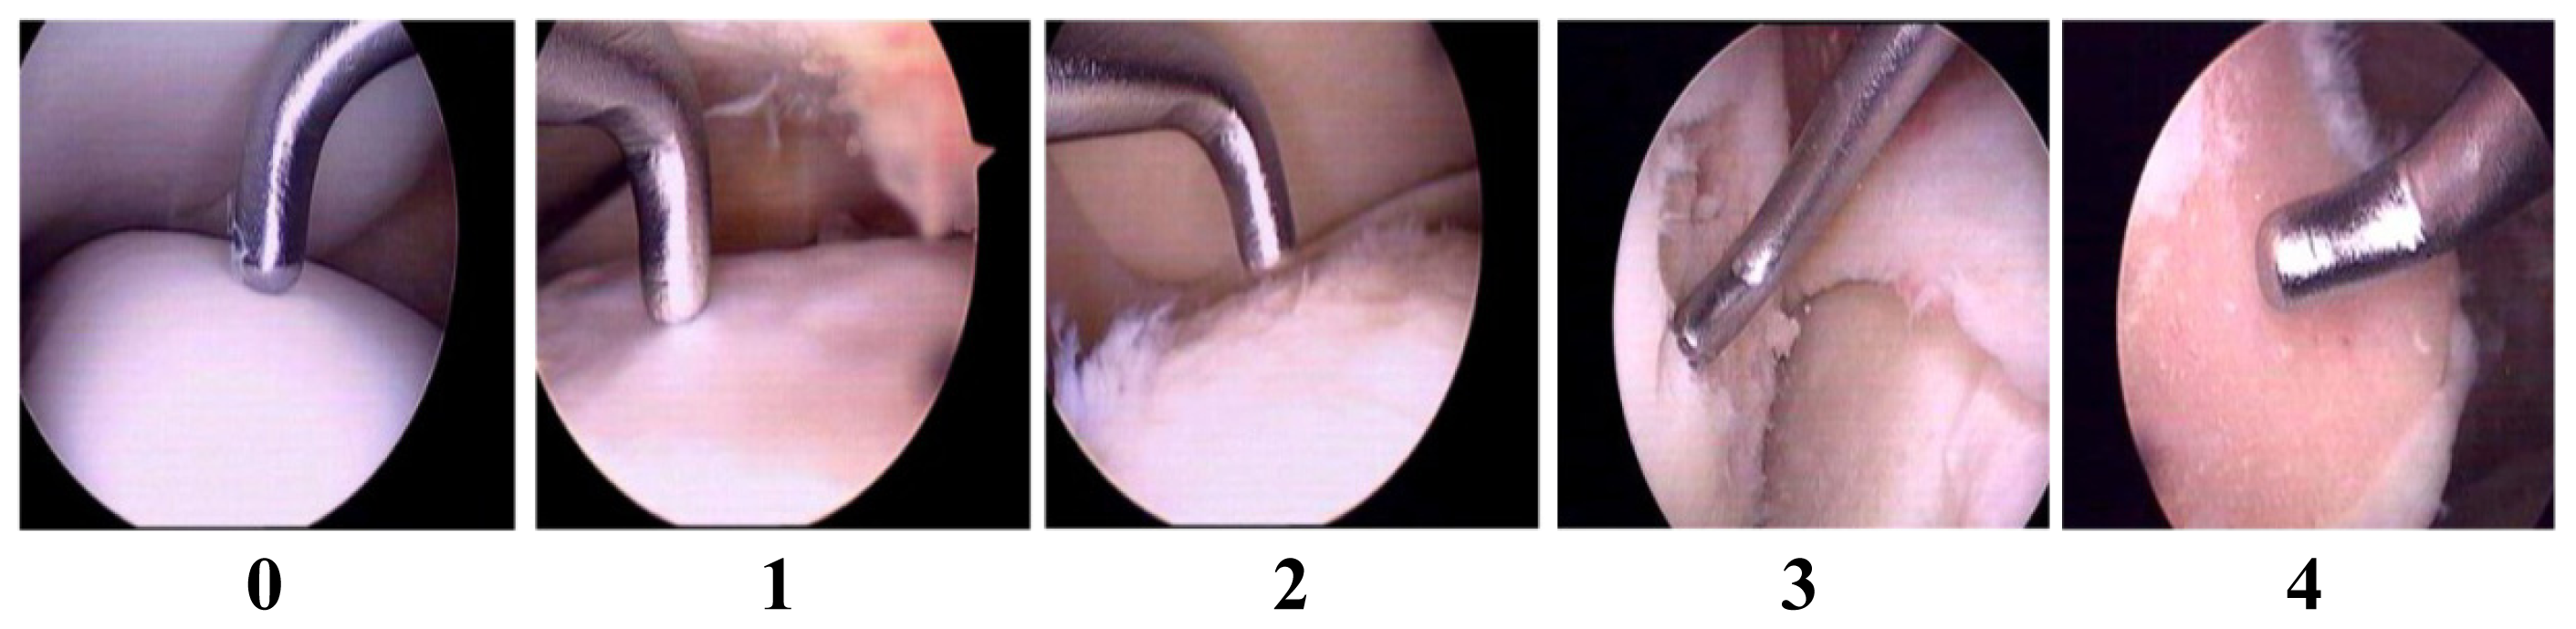

2.1. Validation of Articular Cartilage Lesions in Human Knee Joints Using the Outer-Bridge Scoring System

- Wu, C.W.; Morrell, M.R.; Heinze, E.; Concoff, A.L.; Wollaston, S.J.; Arnold, E.L.; Singh, R.; Charles, C.; Skovrun, M.L.; FitzGerald, J.D.; et al. Validation of American College of Rheumatology classification criteria for knee osteoarthritis using arthroscopically defined cartilage damage scores. Semin. Arthritis Rheum 2005, 35, 197–201. [Google Scholar]

- Cameron, M.L.; Briggs, K.K.; Steadman, J.R. Reproducibility and reliability of the outer-bridge classification for grading chondral lesions of the knee arthroscopically. Am. J. Sports Med 2003, 31, 83–86. [Google Scholar]